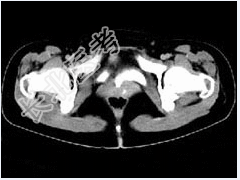

- 多项选择题女,28岁, 阴道有异常液体流下,CT和MRI扫描如图, 以下诊断正确的是( )

B、CT增强示造影剂由膀胱进入阴道

C、膀胱后下缘可见鸟嘴状突起

D、考虑为膀胱阴道瘘

E、考虑为左侧输尿管异位开口